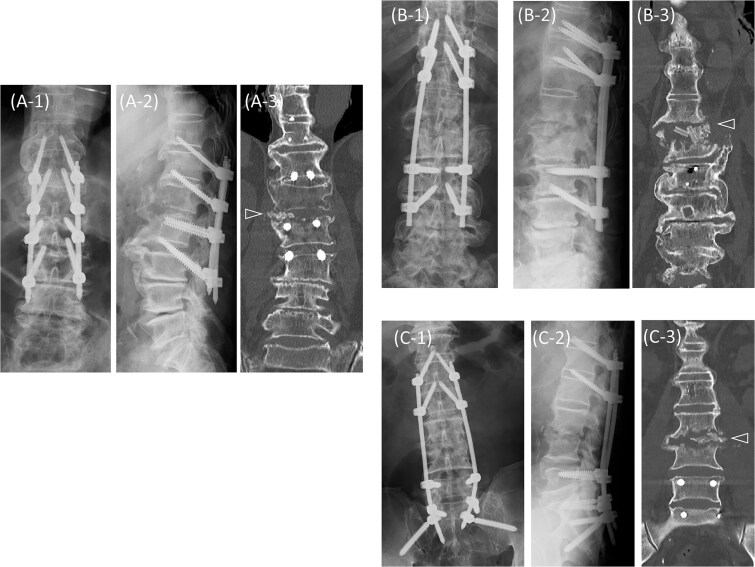

化脓性脊柱炎和弥漫性特发性骨骼肥厚症(DISH)都可以发生在老年人的胸腰椎。在化脓性脊柱炎患者中,据报道,DISH患者的死亡率明显高于非DISH患者。然而,死亡率增加的原因和预防致命后果的有效战略仍有待确定。在这里,我们报告三例化脓性脊柱炎影响非强直性病变的老年DISH患者。这些患者成功地使用穿透性终板螺钉进行前后固定,提供牢固的固定,在DISH中特别有利。对于伴有非强直性病变的化脓性脊柱炎患者,在计算机断层扫描和磁共振成像的指导下,采用穿透性终板螺钉进行早期脊柱固定,可能有助于防止老年患者卧床不起。

Both pyogenic spondylitis and diffuse idiopathic skeletal hyperostosis (DISH) can develop in the thoracolumbar spine of older adults. Among patients with pyogenic spondylitis, those with DISH reportedly have a significantly higher mortality rate than those without DISH. However, the reasons for this increased mortality and effective strategies for preventing fatal outcomes remain to be determined. Here, we report three cases of pyogenic spondylitis affecting non-ankylotic lesions in older patients with DISH. These patients were successfully treated with anterior and posterior fixation using penetrating endplate screws, which provide strong fixation and are particularly advantageous in DISH. In cases of pyogenic spondylitis involving non-ankylotic lesions in DISH, early spinal fixation with penetrating endplate screws, guided using computed tomography and magnetic resonance imaging, may help prevent older adult patients from becoming bedridden.